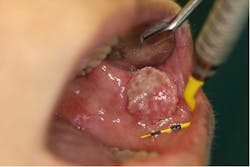

Oral candidiasis

Oral candidiasis (figure 4) is a fungal infection caused by Candida albicans that occurs secondarily to immune suppression. The most common oral form, acute pseudomembranous candidiasis, presents as a white, red, or mixed-color lesion. Findings occur in ages ranging from infants through seniors and immunocompromised populations. Most often, oral candidiasis is displayed as a white patch that can be “easily removed with gauze.”5 This is a key sign that helps distinguish this lesion from others. Candidiasis lesions are often asymptomatic and can be found on the tongue, labial and buccal mucosa, gingiva, hard and soft palates, and the oropharynx. Sometimes symptoms include a burning sensation, bleeding, and changes in taste perception. Initial treatment includes oral antifungal pastilles such as nystatin.5